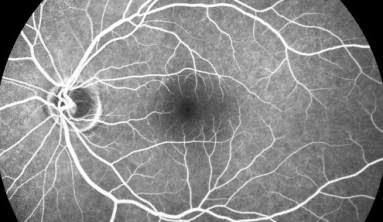

A retinografia é uma foto da sua retina e do nervo óptico que utilizamos para documentar o estado atual das estruturas intra oculares e comparar futuramente.

Fotografia para documentação das alterações retinianas.

Exame que avalia a retina, seus vasos sanguíneos e possíveis lesões da retina e nervo óptico através da injeção de um contraste intra venoso. Após a infusão desse contraste, são tiradas diversas fotos da retina e acompanhamos qual comportamento desse contraste e das estruturas retinianas para nos auxiliar no diagnóstico e acompanhamento das patologias oculares.

O OCT de retina é um tomógrafo capaz de avaliar a retina tirando diversas fotografias da mesma e fazendo reconstruções que simulam cortes histológicos da mesma (analise de cada camada de células de retina) que nos ajudam a identificar precisamente qual parte da retina está danificada para podermos definir qual diagnóstico e qual melhor tratamento.